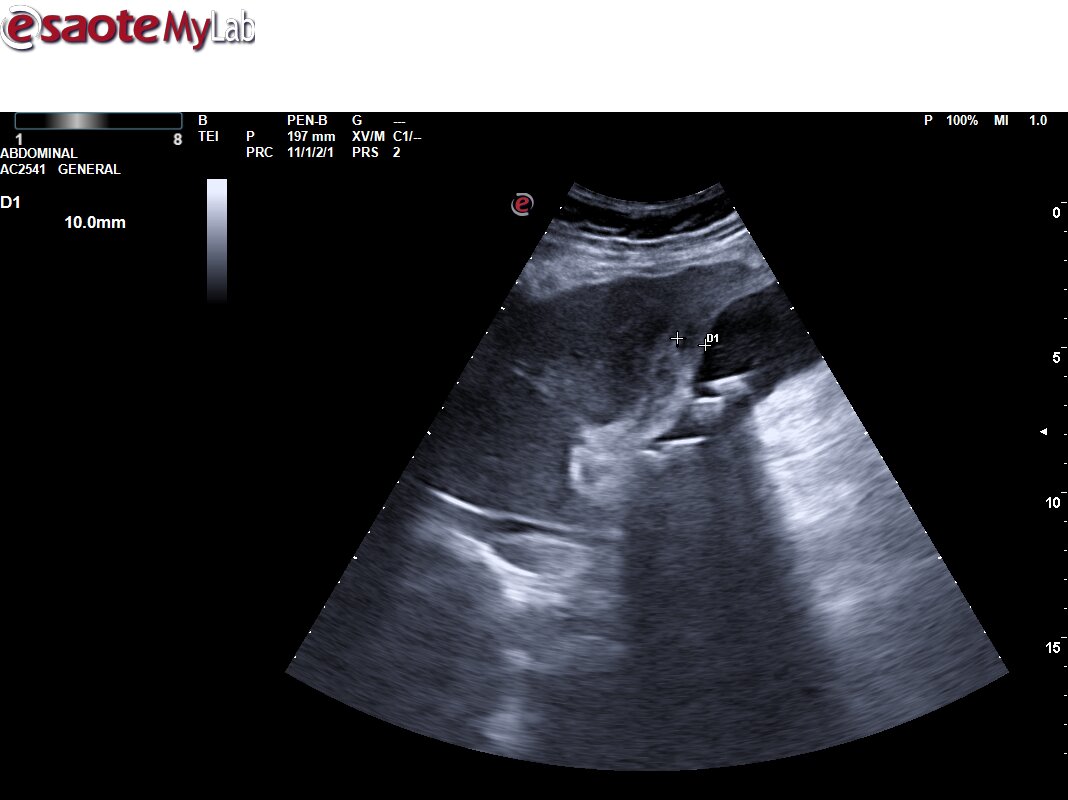

Ecografía Urgencias: Vesícula biliar de tamaño normal, con engrosamiento de la pared con edema de la mucosa. Pequeña colección perivesicular entre la pared vesicular y el reborde hepático de unos 10 mm de grosor, pérdida de continuidad de la pared vesicular compatible con pequeña perforación. Mínima lámina de líquido libre adyacente a la misma. Asocia también abundante contenido hiperecogénico en su interior en relación con barro biliar y varias litiasis en el infundíbulo vesicular. EcoMurphy +. Hallazgos sugestivos de colecistitis aguda complicada con colección / Abceso perivesicular. No líquido libre en los espacios abdominales explorados.